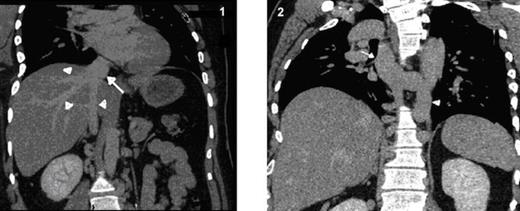

The absence of the right common iliac vein, right external & internal iliac veins and right proximal common femoral vein was also seen. Left external & internal iliac veins drains into the retroperitoneal collaterals due to absence of left common iliac vein. The hepatic veins demonstrate drainage into intrahepatic segment of IVC (Fig. 1).

Coronal MPR CT image shows hepatic veins (arrow heads) seen draining into the intra-hepatic segment of IVC (arrow)